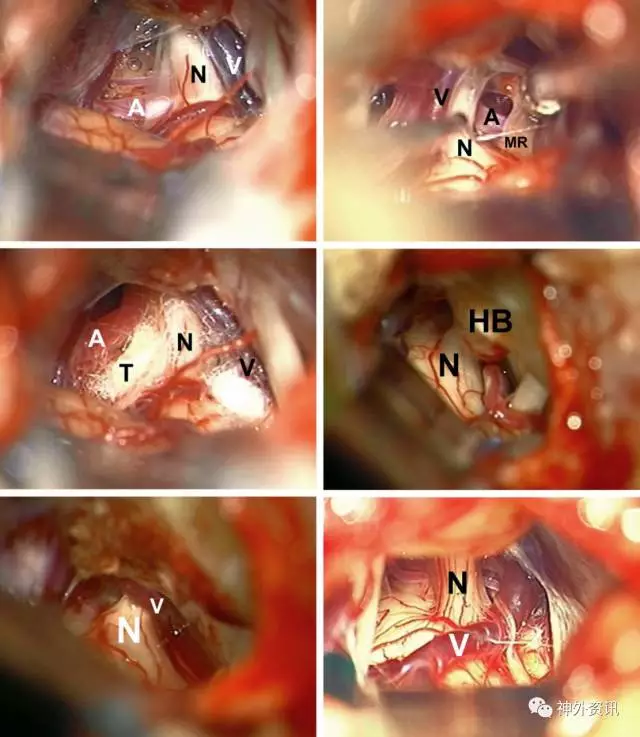

神经血管接触的变异

图16. 微血管减压术术中照片:通常有多条责任动脉(A)和责任静脉(V),上一条责任动脉隐藏在三叉神经运动根(MR)后方(左上图和右上图)。使用Teflon棉可以完整地隔开侵犯的动静脉袢(左中图)。过度增生的岩骨隐藏了血管袢(右中图)。通过磨平过度增生的岩骨,可显露出之前隐藏的血管袢(左下图)。静脉袢也可能是血管压迫的唯一来源(右下图)。